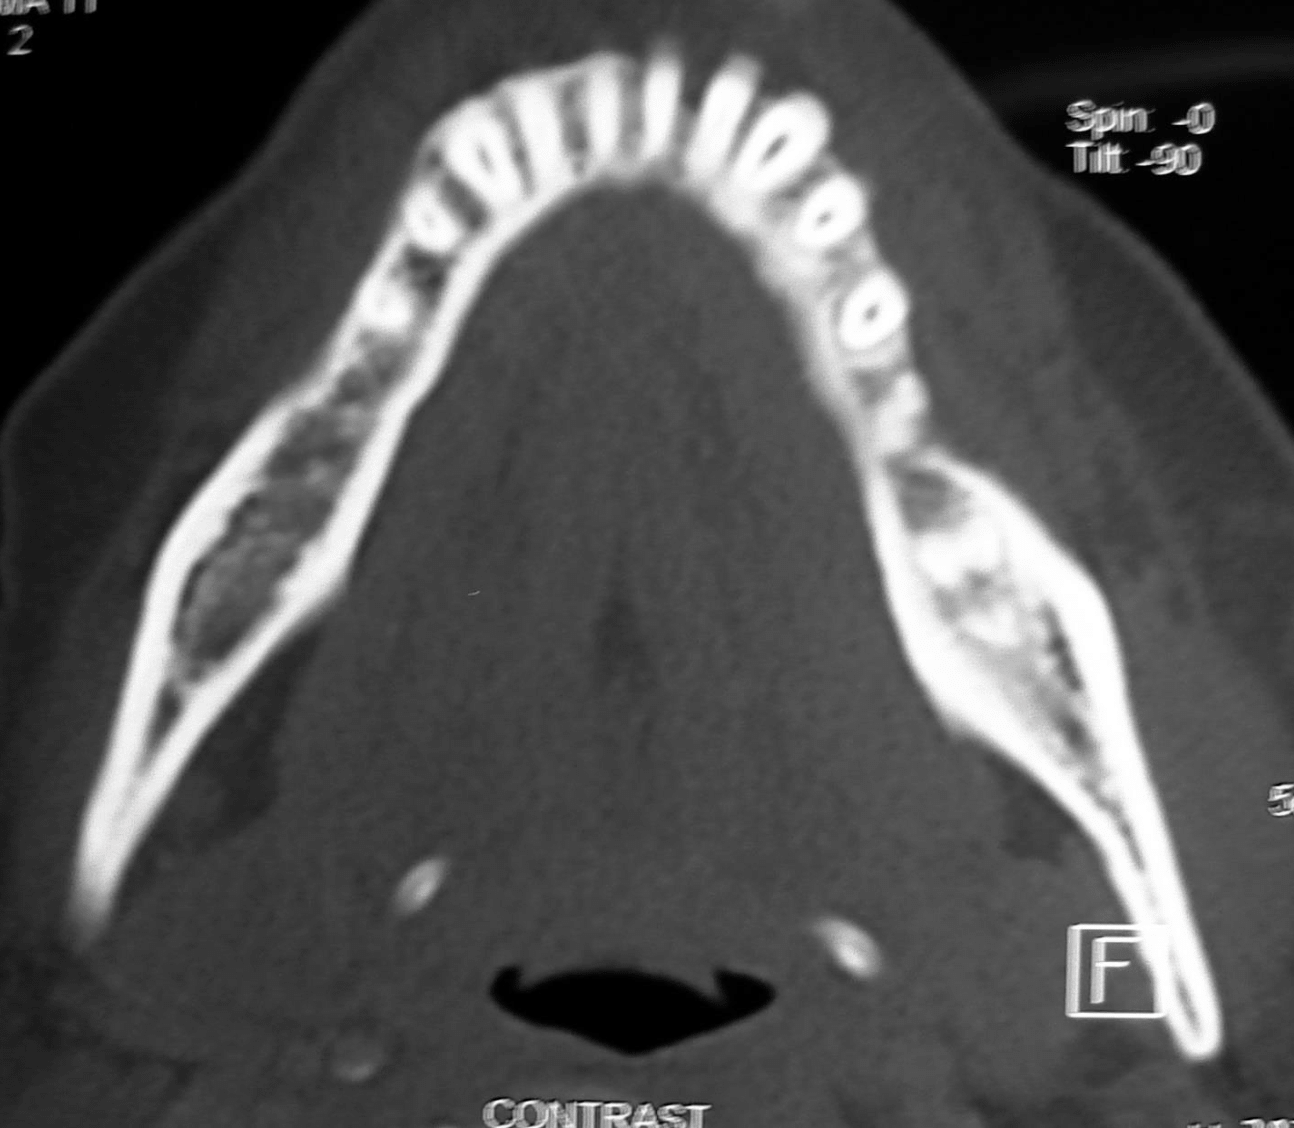

Preoperative radiographic examination including panoramic X-ray and C.T for evaluation of mandibular bone invasion by the lesion and evaluation of the neck lymph nodes (Figure 2A, B, C). Both the mandibular bone and neck lymph nodes were free. Whole body scan with Technetium-99m radiopharmaceuticals imaging was negative (Figure 2D). Clinical stage according to TNM system was T1N0M0.

Figure 2a CT axial view for evaluation of bone invasion by GSCC.

Figure 2b CT axial view for evaluation of bone invasion by GSCC.